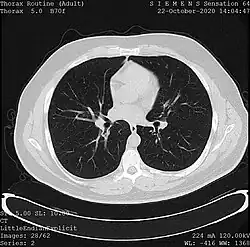

![]() One frame of a CT scan of the chest showing the heart and lungs | |